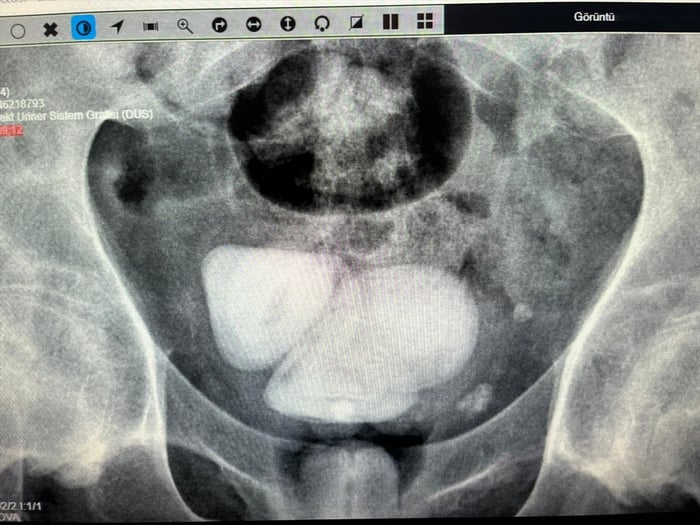

Aydın'da felçli bir hastanın mesanesinden 4 santimetre çapında biri üçgen diğerleri piramit şeklinde 4 taş çıkarıldı.